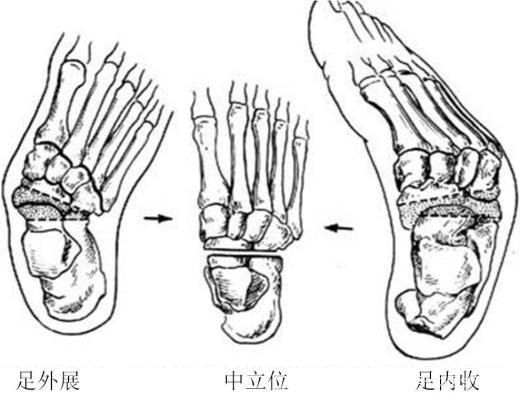

- 足内翻畸形

足内翻的影像学表现